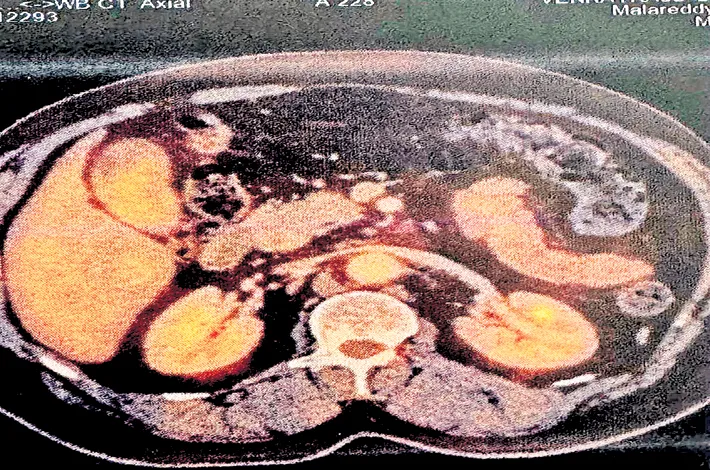

Malla Reddy Narayana Multispeciality Hospital (MRNH) on Friday successfully treated an extremely rare and complex case of gallbladder cancer in a 54-year-old male, where cancer-related tumor emboli were present in the bile duct without the usual symptom of jaundice — a presentation rarely reported in medical literature. The highly intricate surgery was performed by Dr. M. Manisegaran, Director – Minimal Access, HPB&GI Onco Surgeries at MRNH.

The patient, a known diabetic and hypothyroid, approached MRNH with only mild abdominal discomfort. Further investigations revealed a rare and complex combination of conditions: A large gallbladder tumour, multiple tumour emboli inside the Common Bile Duct (CBD), a type IV-A choledochal cyst (bile duct abnormality), associated liver cirrhosis.

In this patient, the bile duct contained multiple cancer deposits. Normal bile flow was maintained. No clinical or laboratory signs of jaundice were present. This unusual presentation posed both a diagnostic and surgical challenge. The patient responded well to the surgery and is currently recovering under the combined care of HPB Surgery, Gastroenterology, and Critical Care teams.